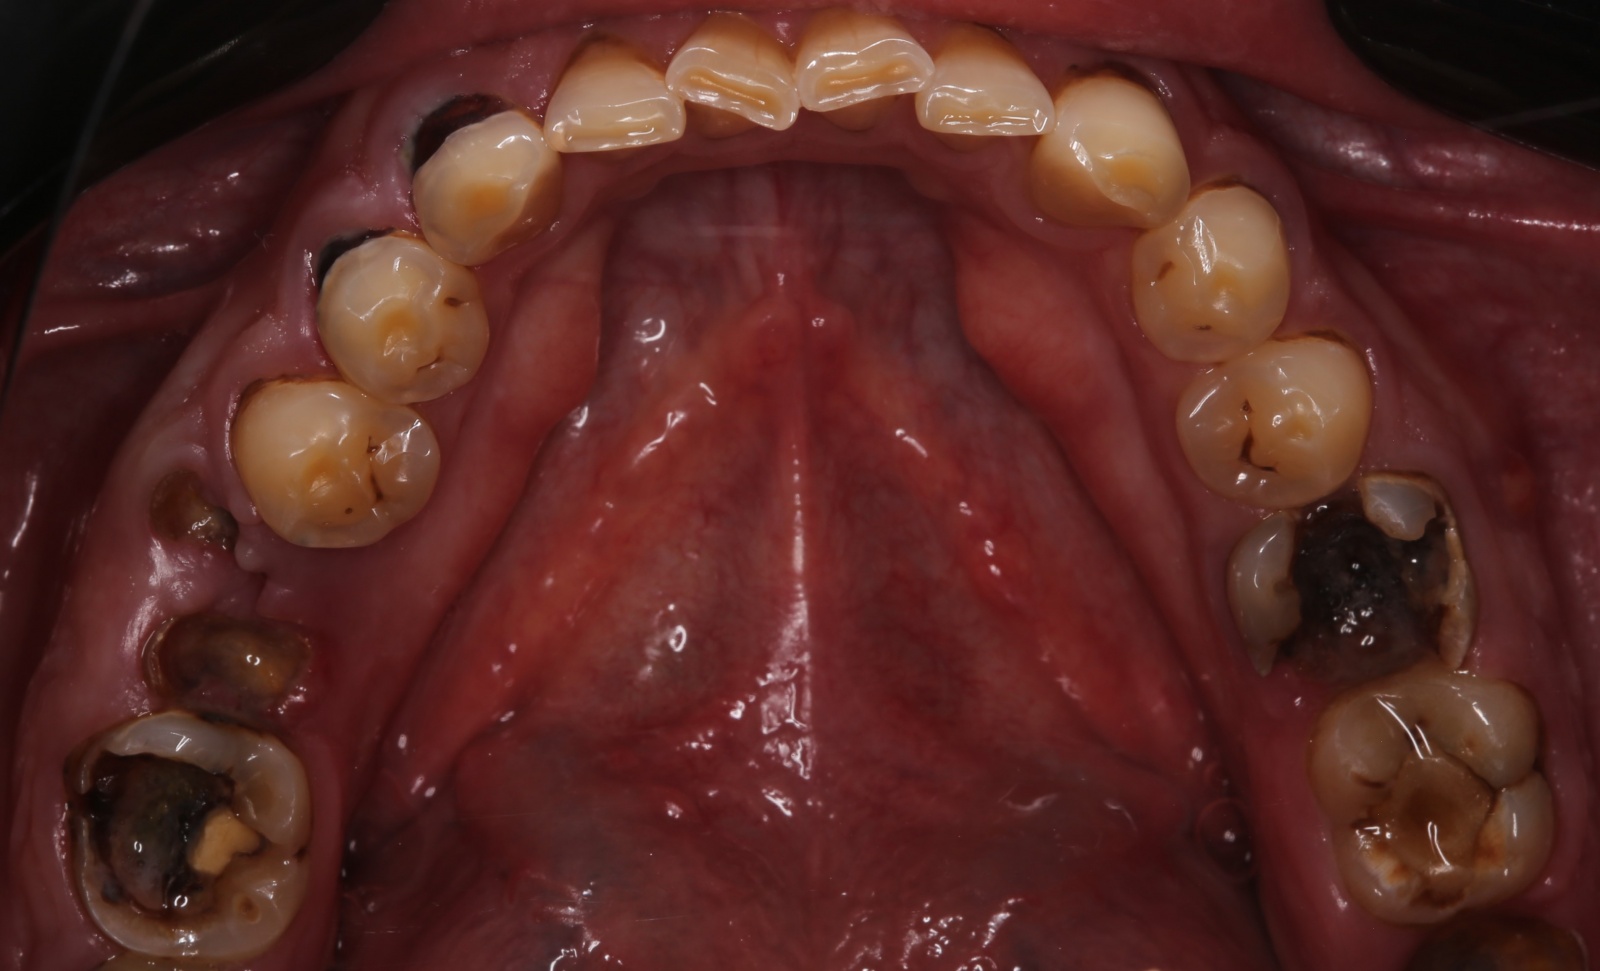

На нижней челюсти у него жевательных зубов не было вообще:

С верхней было немного получше, но не так чтобы сильно:

Такие разрушенные зубы, заросшие десной, кричат о необходимости имплантации

Кариозные процессы сигналят о терапевтической реабилитации и терапевтической санации полости рта

Воспалённые дёсны намекают на пародонтологию